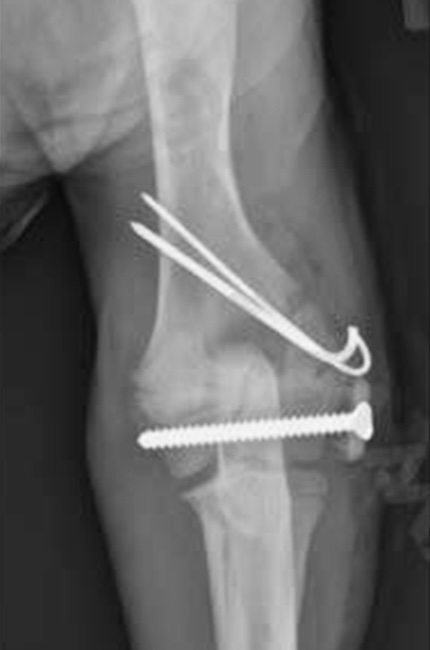

Le traitement est, comme pour beaucoup de fractures chez le chien, chirurgical. Il faut alors réduire la fracture pour réaligner les abouts osseux et maintenir l’os dans sa conformation naturelle puis la stabiliser avec des implants, le plus souvent des broches qui limitent moins la croissance.

La fracture est réduite, le plus souvent avec des broches et parfois des vis. La quantité de matériel orthopédique est limitée afin de traumatiser le moins possible l’os en croissance. Des radiographies sont réalisées après l’intervention.

Le retrait du matériel orthopédique (broches et vis) est parfois recommandé après consolidation osseuse.